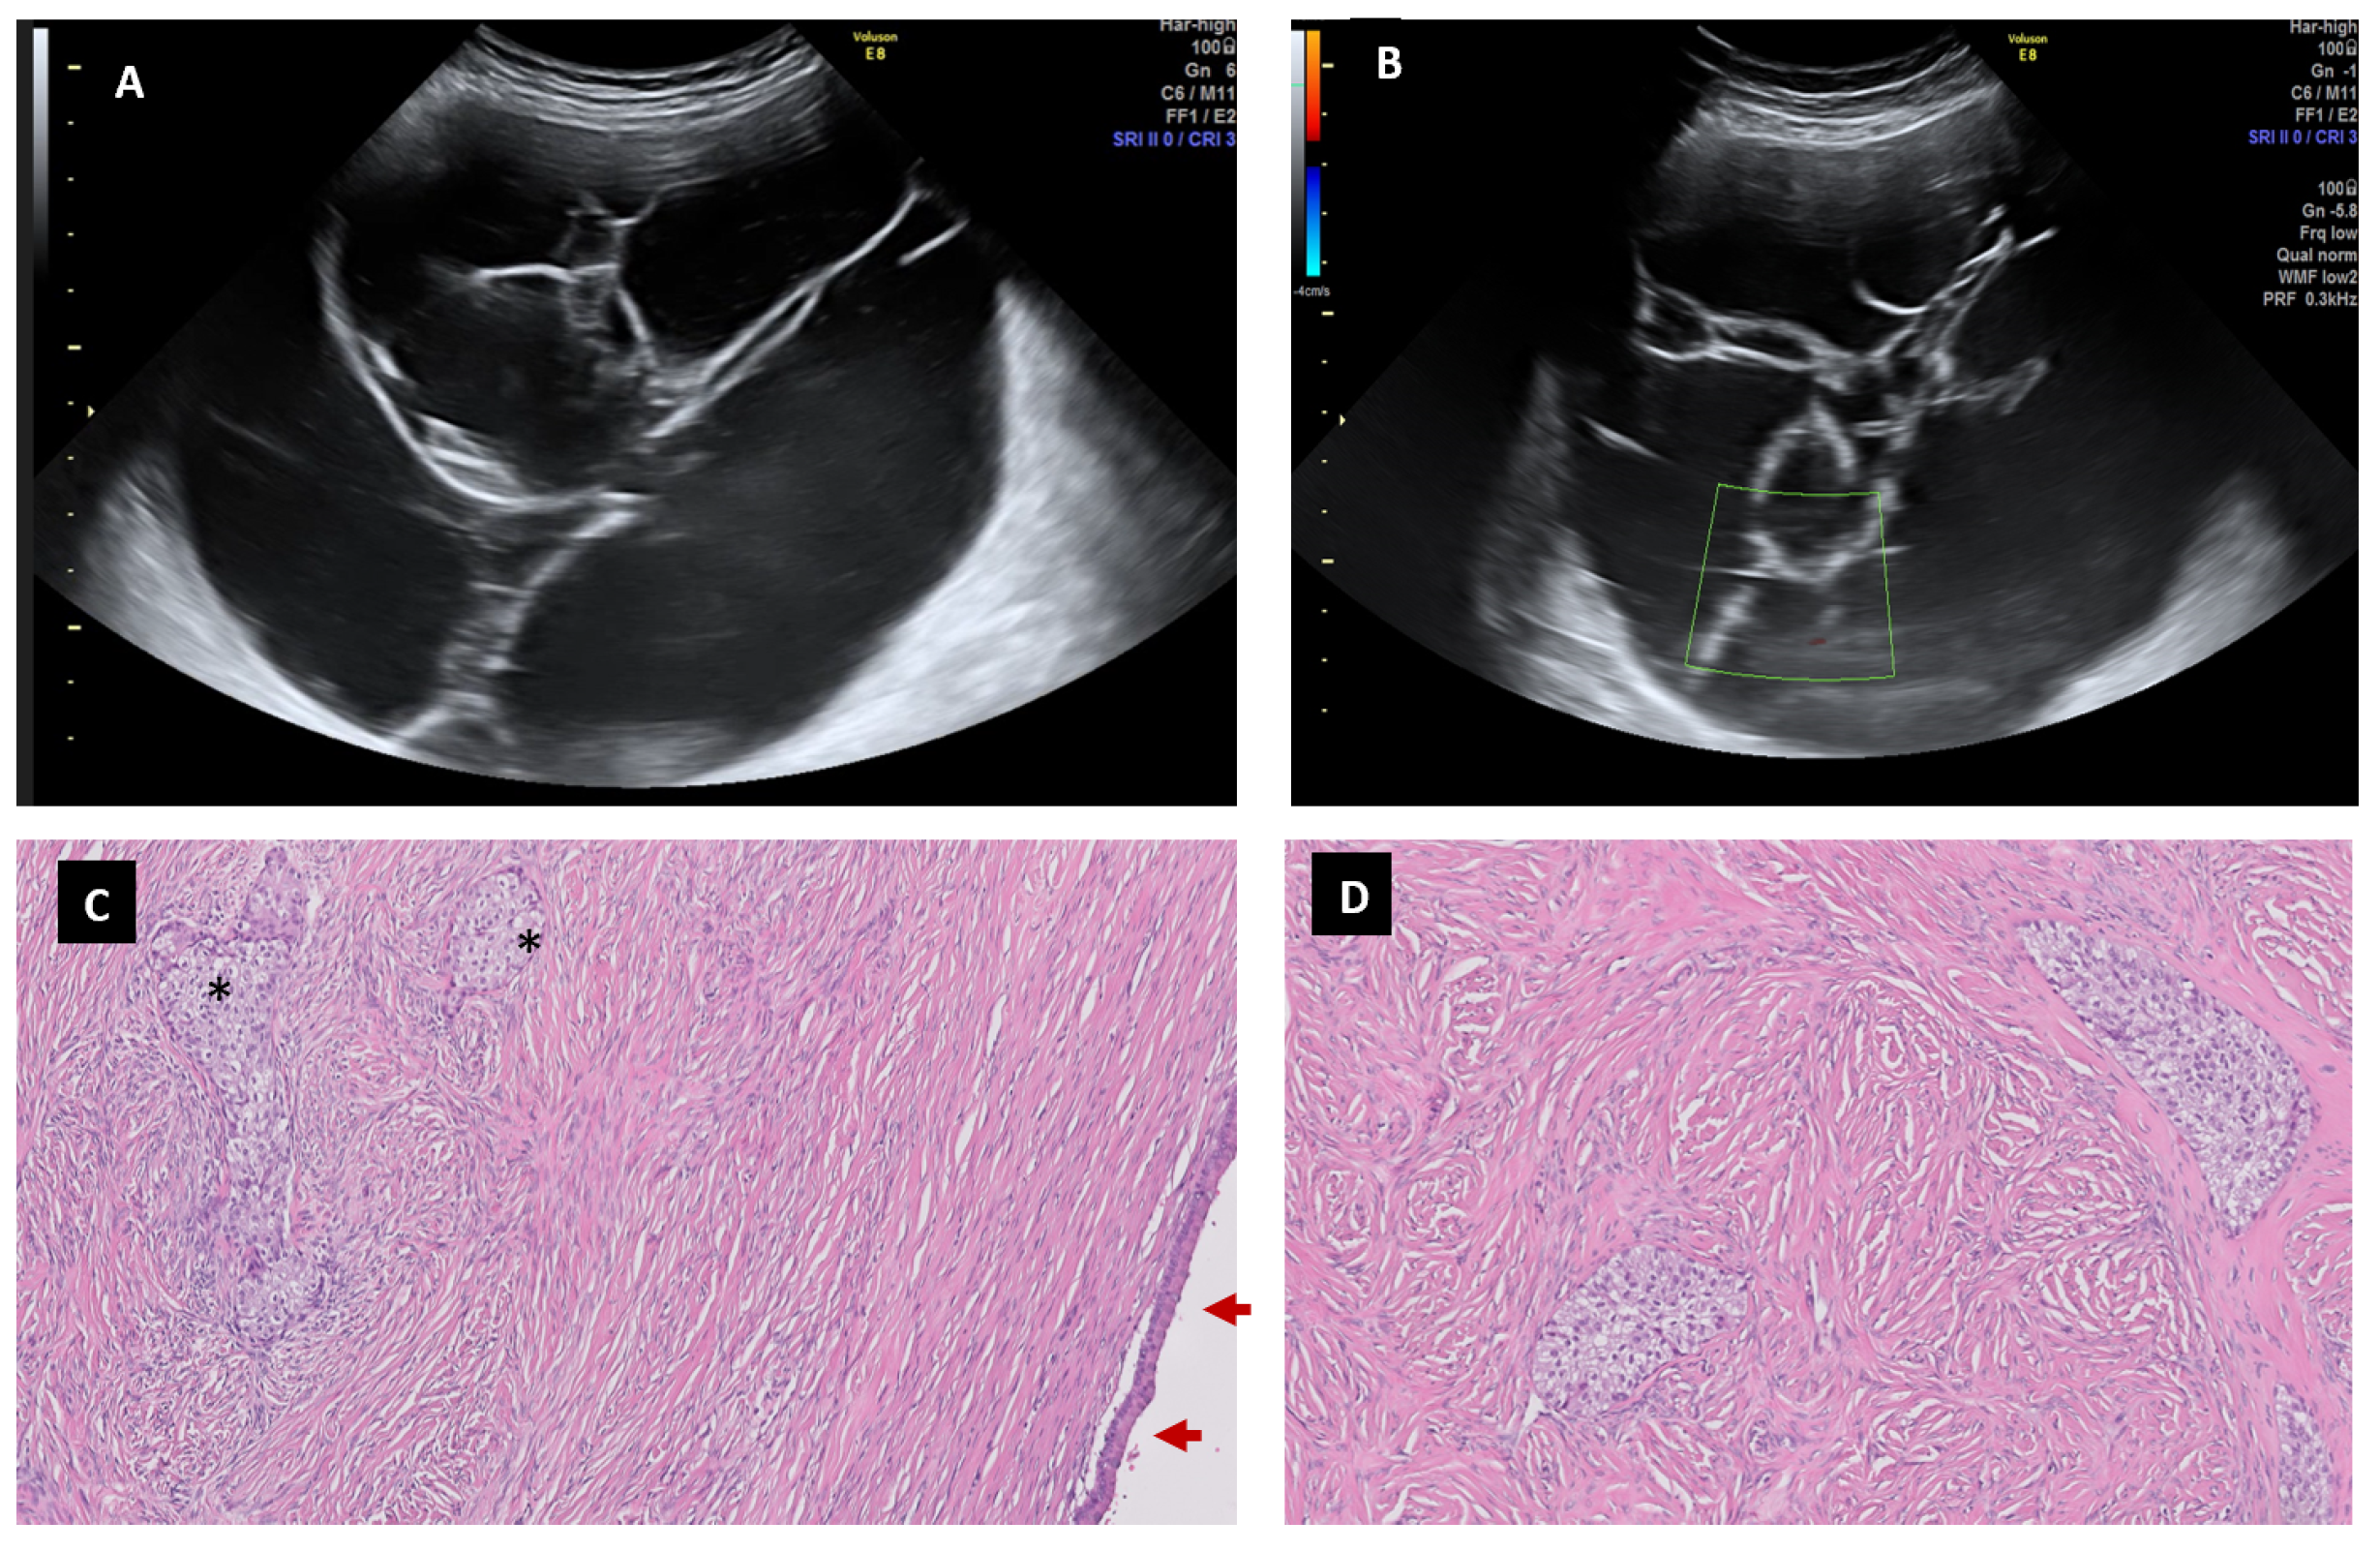

6.6. Brenner Tumor

6.7. Borderline Carcinoma